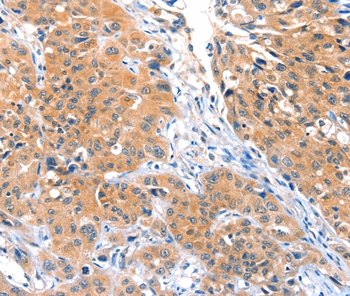

Immunohistochemical analysis of paraffin-embedded Human lung cancer tissue using #36022 at dilution 1/25.